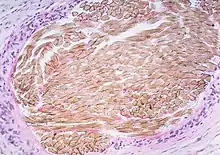

| Picture of a granuloma (without necrosis) as seen through a microscope on a glass slide. The tissue on the slide is stained with two standard dyes (hematoxylin: blue, eosin: pink) to make it visible. The granuloma in this picture was found in a lymph node of a patient with Mycobacterium avium infection | |

Granuloma without necrosis in a lymph node of a person with sarcoidosis.